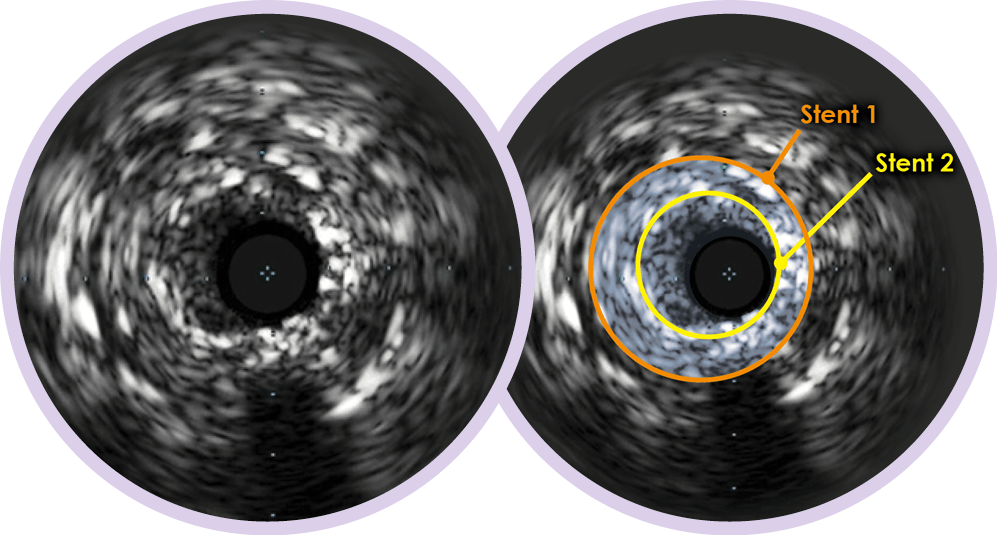

При использовании ВСУЗИ в качестве методики контроля общая летальность в долгосрочной перспективе снизилась на 76%.10 ВСУЗИ помогает определить: • Истинное местоположение устья для снижения риска лечения не того участка сосуда • Расположение бляшки • Необходимость в установке двух стентов • Протяженность поражения • Зону имплантации • Необходимость в постдилатации (в особенности в проксимальном стенте)

ВСУЗИ повлияло на снижение общей летальности в долгосрочной перспективе на 76%10. ВСУЗИ помогает определить: • Истинное местоположение устья для снижения риска лечения не того участка сосуда • Расположение бляшки • Необходимость в установке двух стентов • Протяженность поражения • Зону имплантации • Необходимость в постдилатации (в особенности в проксимальном стенте)